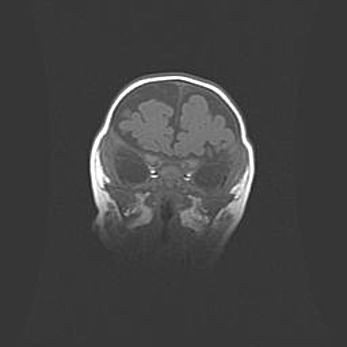

Наружная гидроцефалия с возможной атрофией височных областей.

Возраст: 28 дней

Вес: 3670 г

Пол: мужской

Окружность головы: 38 см

Срок гестации: 40 недель

Гидроцефалия головного мозга у новорожденных – это заболевание, которое характеризуется скоплением избыточного количества спинномозговой жидкости в желудочковой системе головного мозга в результате затруднения её перемещения от места выработки к месту поглощения в кровеносную систему или вследствие нарушения абсорбции. При открытой наружной форме гидроцефалии у новорожденных расширяются и переполняются субарахноидные пространства.

При нормотензивных  формах,  которые,  как  правило,  являются  следствием  перенесенных ишемических  повреждений  паренхимы  мозга,  возможно  сочетание микроцефалии  с нормотензивной гидроцефалией. В основе данных изменений лежит атрофия больших полушарий с преимущественной  локализацией  в  лобно-височных  областях.